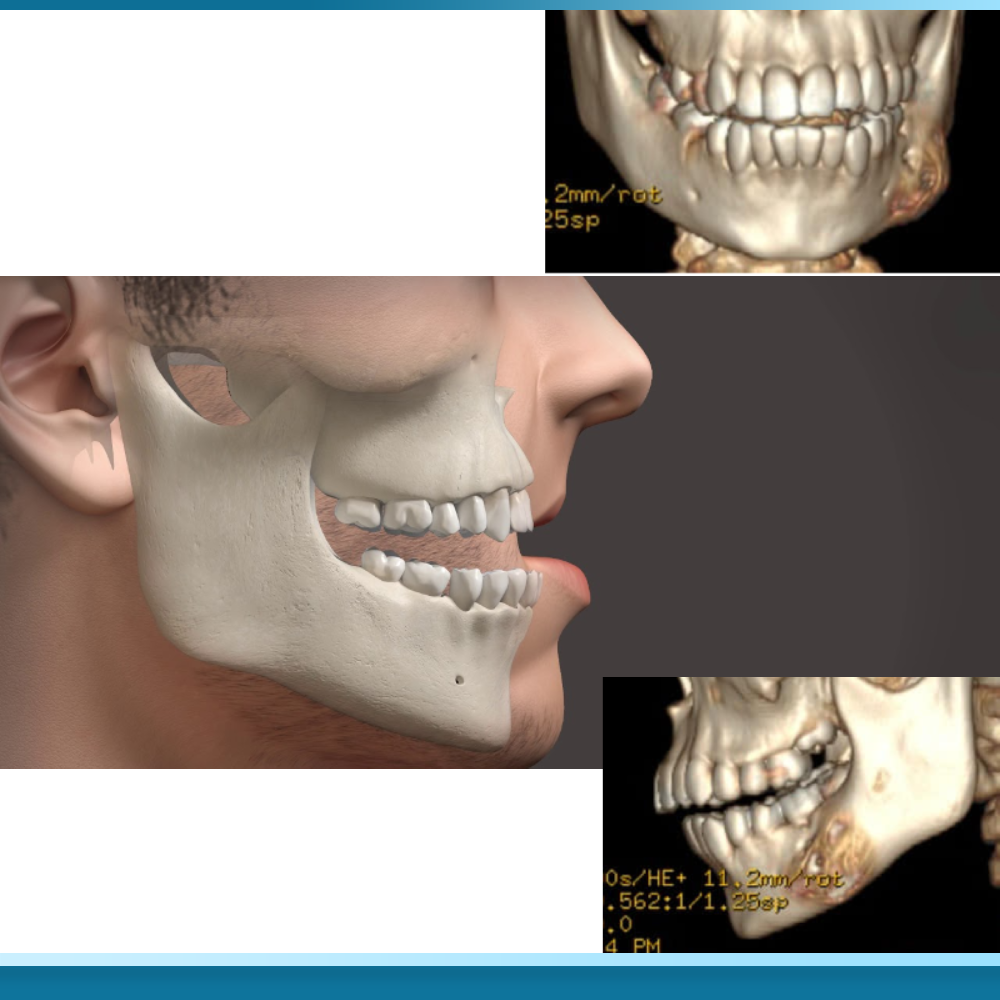

Đánh giá mật độ xương qua phim CT Cone Beam trước khi cấy ghép

Phim chụp CT Cone Beam 3D là công cụ chẩn đoán hình ảnh không thể thiếu để xác định khả năng thực hiện Trồng răng Implant All on 6. Công nghệ này cho phép bác sĩ quan sát cấu trúc xương hàm theo không gian ba chiều, đo lường chính xác chiều cao, chiều rộng và đặc biệt là mật độ xương thông qua chỉ số Hounsfield (HU). Dựa trên phân loại của Misch, mật độ xương được chia thành bốn loại từ D1 đến D4.

Trong đó, D1 là xương đặc nhất (thường ở vùng phía trước hàm dưới) và D4 là xương xốp nhất (thường ở vùng phía sau hàm trên). All on 6 yêu cầu một tỷ lệ xương D1, D2 hoặc ít nhất là D3 ở hầu hết các vị trí đặt trụ để đảm bảo sự ổn định lâu dài.

Trong quá trình khảo sát phim CT, bác sĩ cũng sẽ đánh giá vị trí của xoang hàm và các ống thần kinh. Đối với những bệnh nhân mất răng lâu năm, xoang hàm thường có xu hướng sa xuống thấp, làm giảm đáng kể chiều cao xương ở vùng răng hàm trên.

Nếu kết quả phim chụp cho thấy chiều cao xương còn lại dưới 5-6mm, việc đặt thêm hai trụ phía sau cho All on 6 sẽ trở nên bất khả thi nếu không có các thủ thuật bổ trợ. Việc đánh giá kỹ lưỡng qua phim CT Cone Beam giúp loại bỏ các yếu tố suy đoán cảm tính, đảm bảo rằng mỗi ca phẫu thuật đều được lập kế hoạch dựa trên các dữ liệu khoa học chính xác nhất, từ đó tối ưu hóa tỷ lệ thành công của quá trình tích hợp xương.